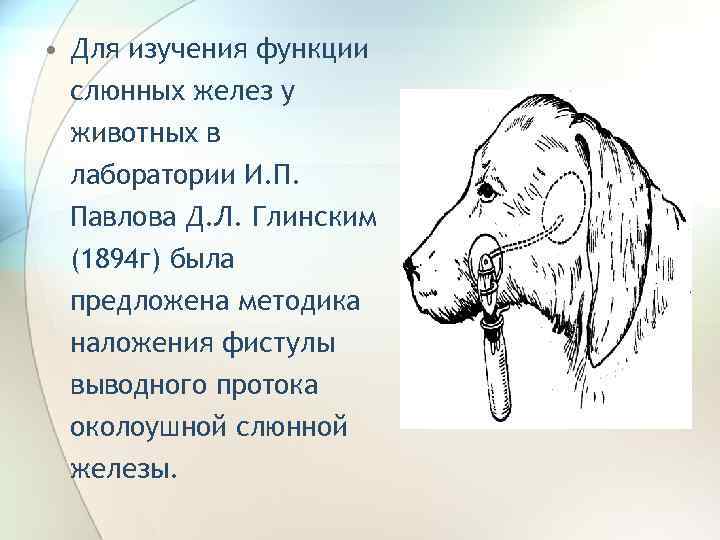

• Для изучения функции слюнных желез у животных в лаборатории И. П. Павлова Д. Л. Глинским (1894 г) была предложена методика наложения фистулы выводного протока околоушной слюнной железы.